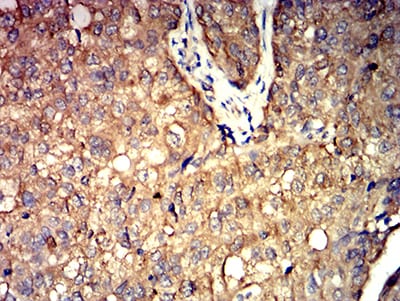

分类: 科研抗体货号: 31277别名: CTNNB; MRD19; armadillo;Beta-catenin应用: WB,IHC,FCM反应种属: Human,Mouse